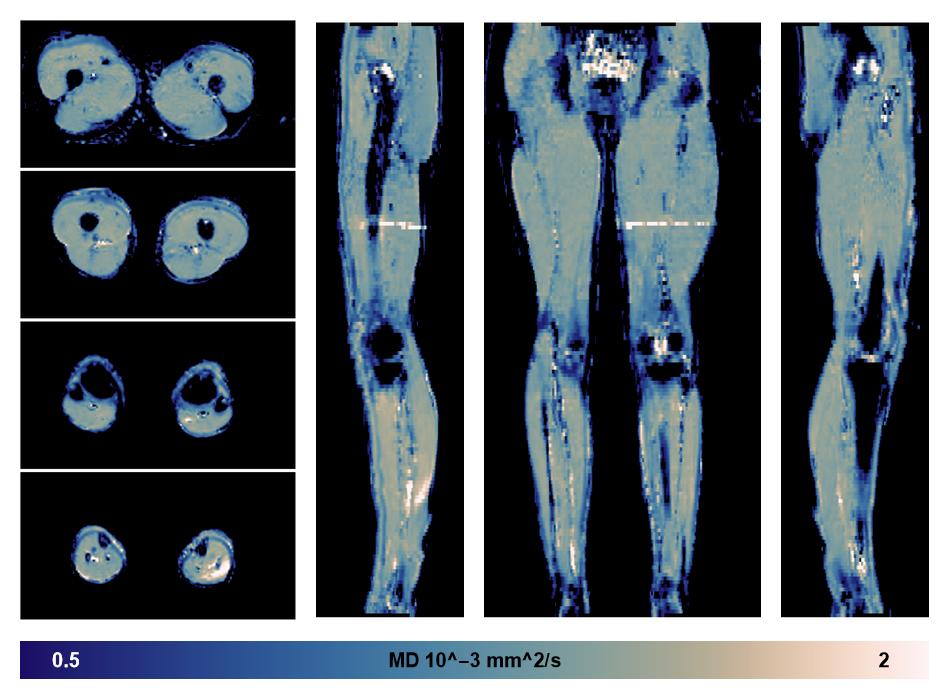

• Mean diffusivity

IVIM corrected whole leg muscle mean diffusivity obtained from diffusion tensor imaging.